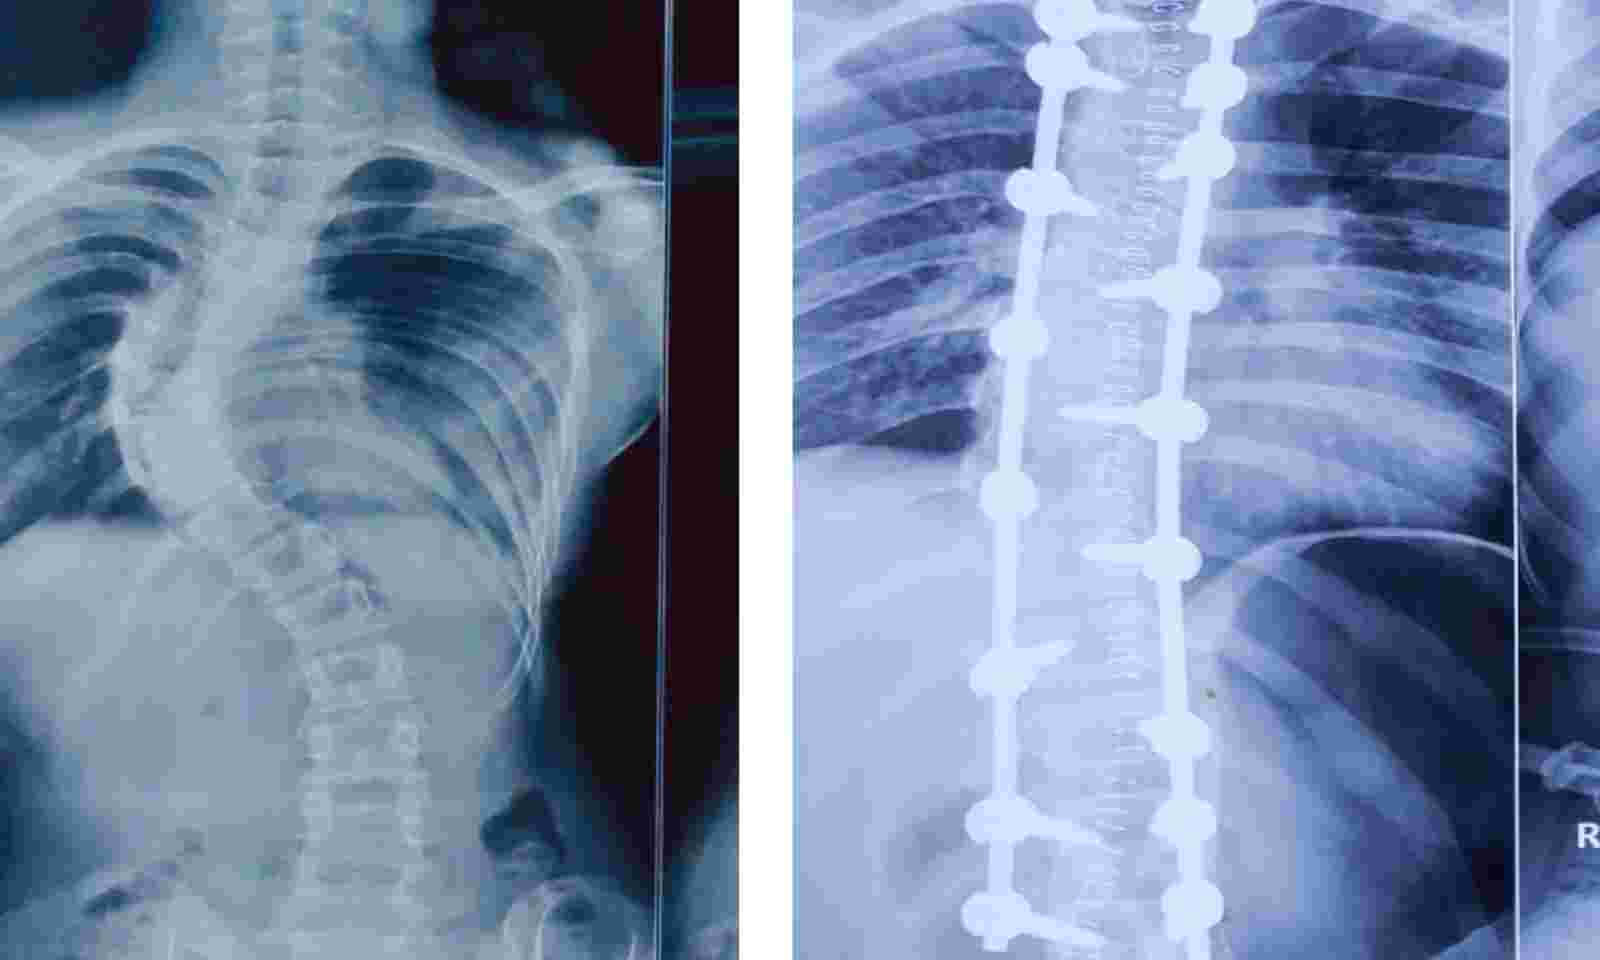

Deformity Correction for Scoliosis

Scoliosis is a spinal deformity where an abnormal curvature in the back is present. Often, this type of deformity will be a curvature to the right or left and sometimes will include a rotational aspect of the spine. This type of deformity occurs in adults and adolescents. In certain patient scenarios, scoliosis reconstructive surgery is discussed to help improve symptoms of pain, numbness, or tingling. In other scenarios this type of deformity correction is discussed after the scoliosis has progressed to a certain degree with the goal to halt any further progression of this abnormal curvature.

Scoliosis and deformity corrective surgeries help to realign the spine in patients with abnormal curvatures.